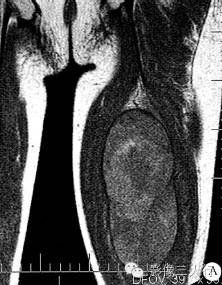

文献报道,血管外皮肉瘤发现时多体积巨大,平均直径8〜10cm。因肿瘤内有坏死、囊变区及纤维组织成分,血管外皮肉瘤在MRI图像上多信号混杂,T1WI为等低信号为主,T2WI不均匀高信号,可伴瘤体内出血。50%以上的血管外皮肉瘤瘤内有扭曲的血管流空征象,可作为该病的特征性表现。但是,海绵状血管瘤和部分恶性纤维组织细胞瘤,因血管丰富,也可有血管流空征象,与之鉴别有困难。

回顾分析,本例因无确切血管流空征象,其MRI表现与软组织肉瘤相仿,定性难度较大。关于肿瘤包膜,较小的血管外皮肉瘤因侵袭性而无明显包膜。但当肿块迅速生长至体积巨大时,多有包膜形成,并且包膜较完整,本例即是如此。因此,对于巨大软组织肿瘤,有无完整包膜对鉴别良、恶性无显著意义。总之,血管外皮肉瘤缺乏特征性临床和影像表现,MRI多方位、多参数成像及增强扫描是显示肿瘤范围、组织成分、包膜及与周边组织关系的最佳方法,最后确诊需组织学与免疫病理。